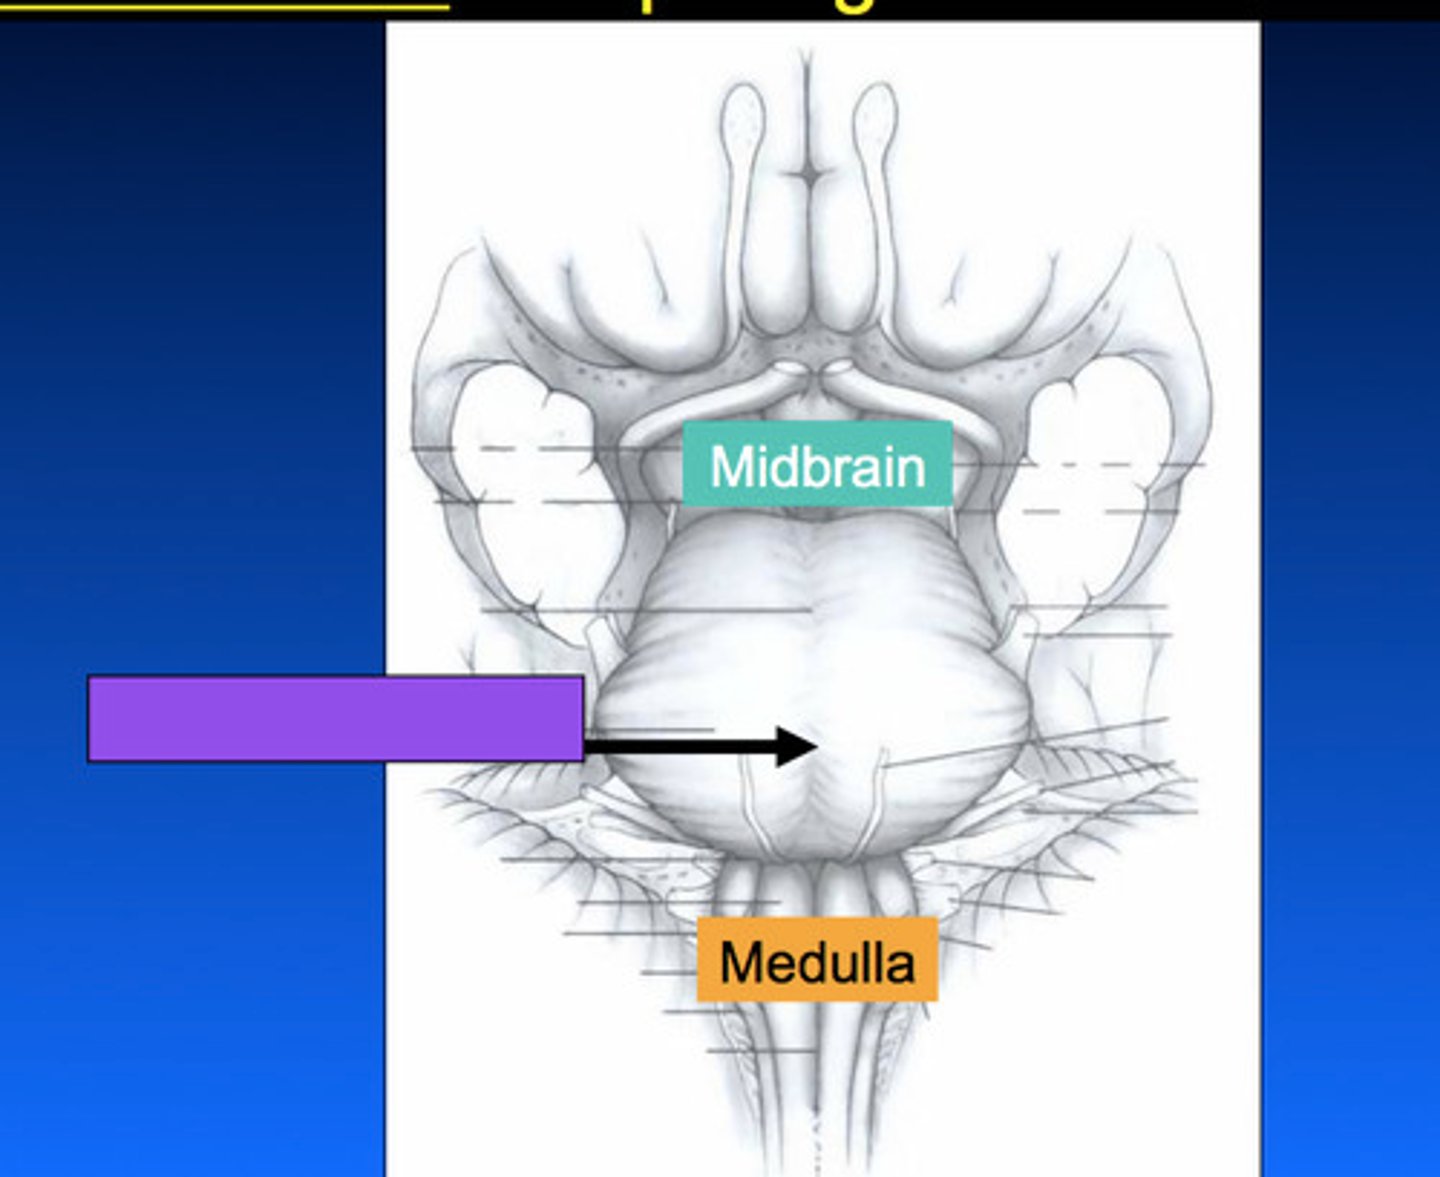

What are the 3 parts of the brain stem?

midbrain, pons, medulla

What is the superior boundary of the pons?

isthmus of the brain stem (between pons and cerebral peduncles)

What is the inferior boundary of the pons?

pontomedullary junction

What is the superior boundary of the midbrain?

just under the mamillary bodies of the diencephalon

What is the inferior boundary of the midbrain?

isthmus of brain stem